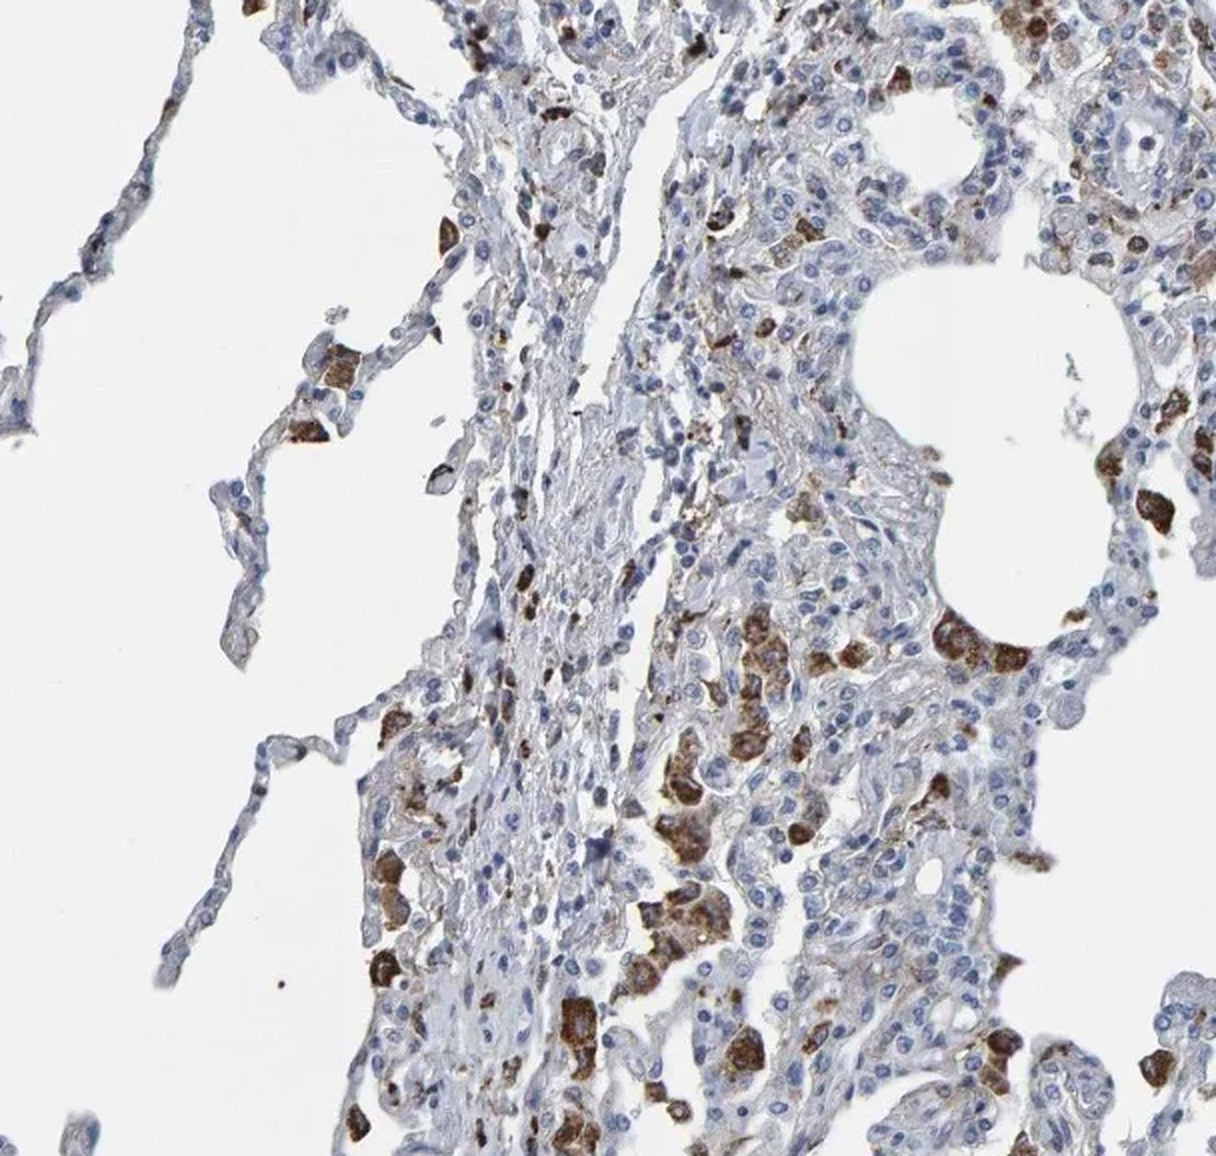

MedVistaGym comprises a set of verifiable medical VQA tasks that demand grounded, multi-step reasoning over visual inputs and intermediate evidence. These tasks span diverse diagnostic scenarios, including clinical perception, lesion-level evidence localization, subtle abnormality detection, and diagnosis-oriented evidence aggregation, where generating reliable answers requires calling external tool support. The training data in MedVistaGym is organized along two complementary axes. (1) Radiology VQA, covering cross-sectional and projection imaging, includes VQA-RAD Lau et al. (2018), which focuses on anatomy and finding recognition in X-ray, CT, and MRI images, and SLAKE Liu et al. (2021), a knowledge-aware dataset with clinically grounded questions over diverse radiology images. (2) Pathology VQA, covering microscopy and histopathology, includes PathVQA He et al. (2020), which emphasizes cellular morphology and tissue patterns. More details are provided in Appendix A.2.